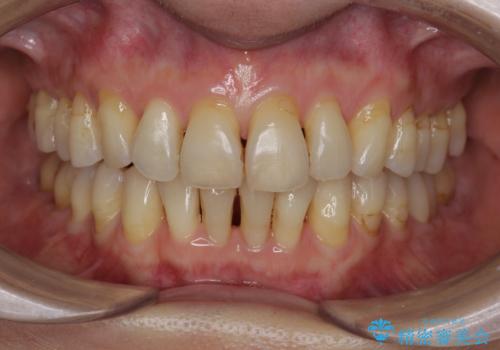

- 歯ぎしりが気になる 歯が将来ダメになるのが怖いとの事で相談を受けた患者様です。

型取り(上下)をして自費のナイトガードを作製しました。